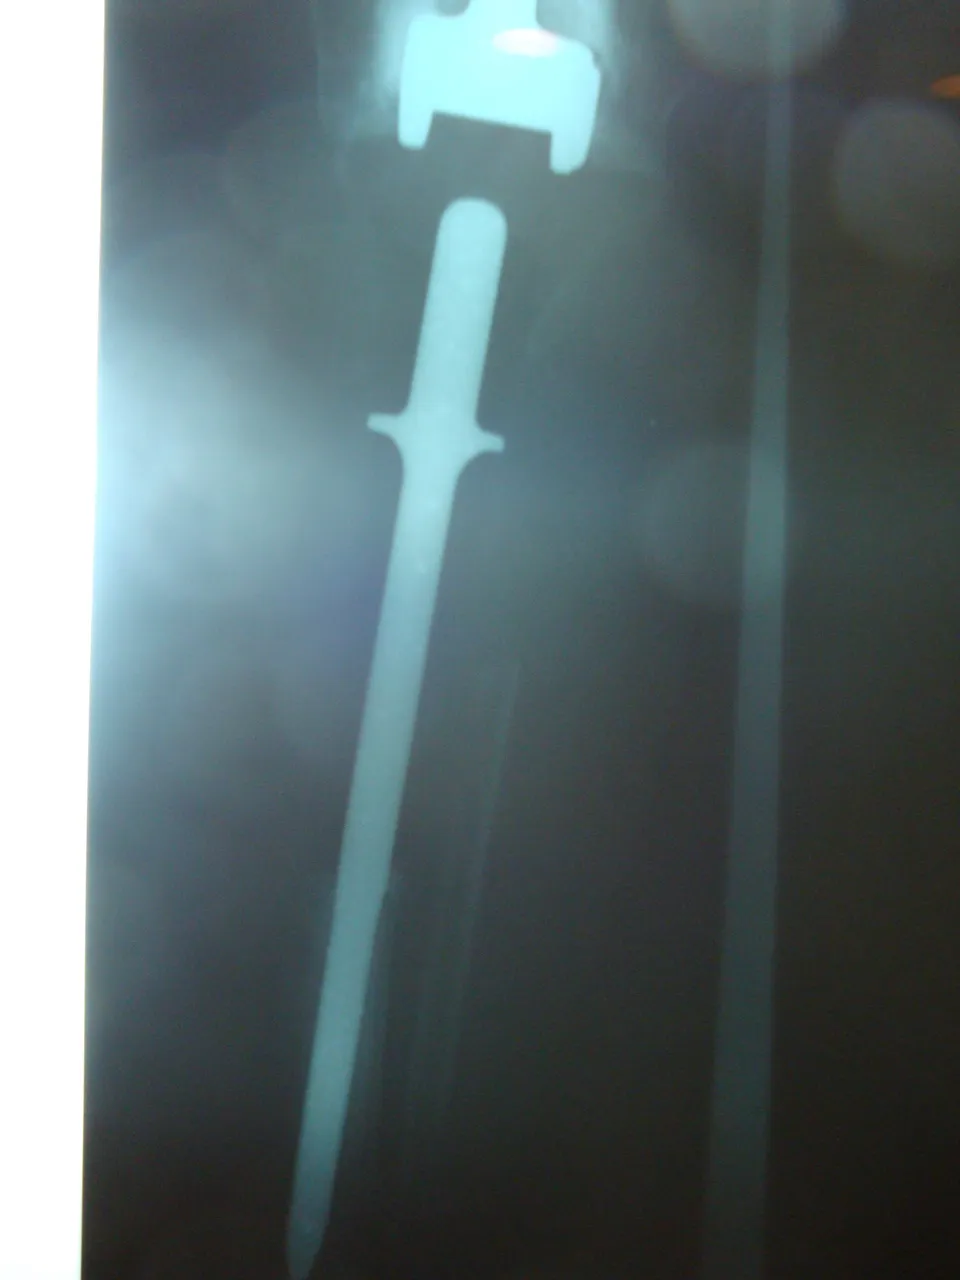

The total knee prosthesis is the reference technique when the tumor is aggressive, extracompartmental and extends to the epiphysis. A constrained total prosthesis is used, preferably a "forced fit", cemented, with long centromedullary stems that rest on the isthmus of the healthy side. The joint is a hinge with or without rotation. When the affectation is femoral without joint invasion, if a subtotal excision of the quadriceps is made, special care must be taken in the reconstruction of the extensor apparatus by means of transfer of the hamstrings.

In femoral tumors, reconstruction is done with a vascularized fibula that is placed in the medial part, with a complementary lateral allograft. Osteosynthesis is done with a plate. In tibial tumors, an allograft maintained with a bolted nail is an effective solution. At present, arthrodesis is restricted to rare cases such as patients with high sports activity or demanding jobs or if there is a risk of significant infection; they are performed with the help of an inverted vascularized fibula. The current therapeutic guidelines are characterised by the reduction of arthrodesis and by the use of prostheses that have demonstrated their longevity and functionality. The recommendation of biological therapies rests on their longevity, as long as they are compatible with a satisfactory oncological removal. This exeresis and reconstruction surgery provides good oncological results, although at the cost of complex interventions that involve frequent substitutions. Only teams familiar with replacement prostheses and the practice of flaps and experts in vascularized bone transfers should make it.